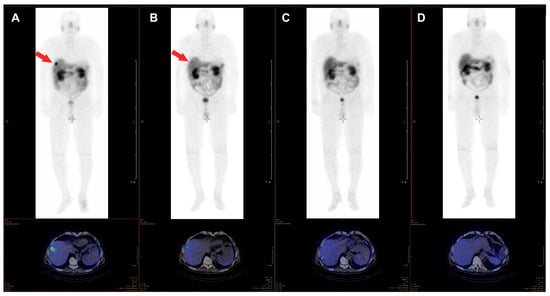

The β-emitter-labeled somatostatin analogue, 177Lu-DOTA-D-Phe-Tyr3-octreotate (DOTATATE), improves PFS, quality of live, and presumably OS. In the NETTER-1 trial, 229 patients with progressive, well-differentiated (G1 or G2) neuroendocrine tumors were randomized to be treated either with 60 mg long-acting octreotide LAR or 177Lu-DOTATATE and 30 mg octreotide LAR [20]. After 20 months, PFS was 62% in the group treated with 177Lu-DOTATATE and 30 mg Octreotide LAR compared with 11% in the Octreotide LAR group. This difference was statistically significant. The response rate was 18% in the group with radionuclide treatment vs. 3% in the group treated with Octreotide LAR. Interestingly, OS was higher in the radionuclide group too, as only 14 deaths occurred in the 177Lu-DOTATATE group compared to 26 in the Octreotide LAR monotherapy group. Radionuclide therapy did not cause increased rates of nephrotoxicity, however, the rate for grade 3 or 4 neutropenia, thrombocytopenia, and lymphopenia was 1%, 2%, and 9% respectively. Octreotide LAR (60 mg/d) monotherapy in contrast was not hematotoxic. In an additional analysis of the NETTER trial data, a higher quality of life was found in patients treated with 177Lu-DOTATATE compared to octreotide LAR monotherapy [21]. An image example of a patient with very good treatment response to 177Lu-DOTATATE is shown in Figure 1. The second example demonstrates a full response achieved with 177Lu-DOTATATE treatment. In Figure 2, images of a patient with pancreatic NETs during four cycles of treatment with a total dose of 28.8 GBq 177Lu-DOTATATE are presented. After the last cycle, no active tumor tissue was found in PET/CT imaging, and also in the follow-up after 6 and 12 months, no tumor localization could be identified, corresponding to a full response.

Figure 2. Example of a 76-year-old male patient with pancreatic NET, first diagnosed in 2012, with an initial ki-67 index of 15% who underwent four cycles of treatment with 177Lu-DOTATATE (cumulative dose 28.8 GBq) between October 2017 and July 2018, due to progression of bilobar liver metastases. The liver metastasis clearly visible in the post-therapy scan of the first cycle (A) is just barely visible in the scan of the second cycle (B) and not visible anymore in the scans of the third (C) and fourth (D) cycle. In the PET/CT images acquired six and twelve months after the last cycle, no tumor tissue was identified.